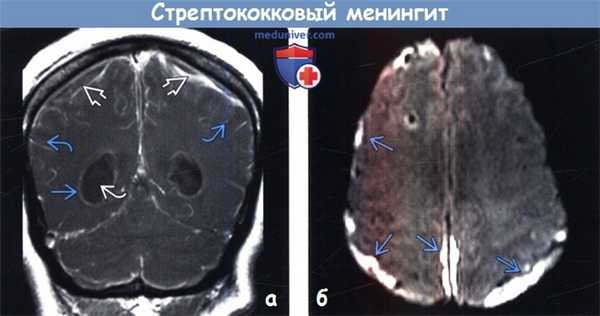

(а) МРТ, постконтрастное Т1-ВИ, корональный срез: у новорожденного с β-стрептококковым менингитом определяется протяженное контрастирование лептоменинкс. Контрастирование эпендимы в сочетании с наличием внутрижелудочкового детрита объясняется вентрикулитом. Обратите внимание на внемозговые скопления жидкости с ободковым характером контрастирования.

(б) МРТ, ДВИ, аксиальный срез: у этого же пациента определяется ограничение диффузии в области субдуральных скоплений жидкости, что характерно для эмпиемы. ДВИ помогает дифференцировать реактивный субдуральный выпот от эмпиемы.